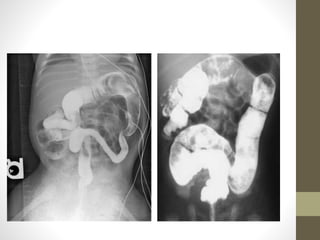

• Plain x-ray abdomen:

• Disparity in the size of the

intestinal loops

• No or few air fluid levels on

erect film

• Granular soap bubble

(Neuhauser sign)

Water soluble contrast

enema:

• Unused or microcolon

often containing small,

inspissated rabbit pellets of

meconium.

• If reflux into the terminal

ileum pellets of meconium

can be seen